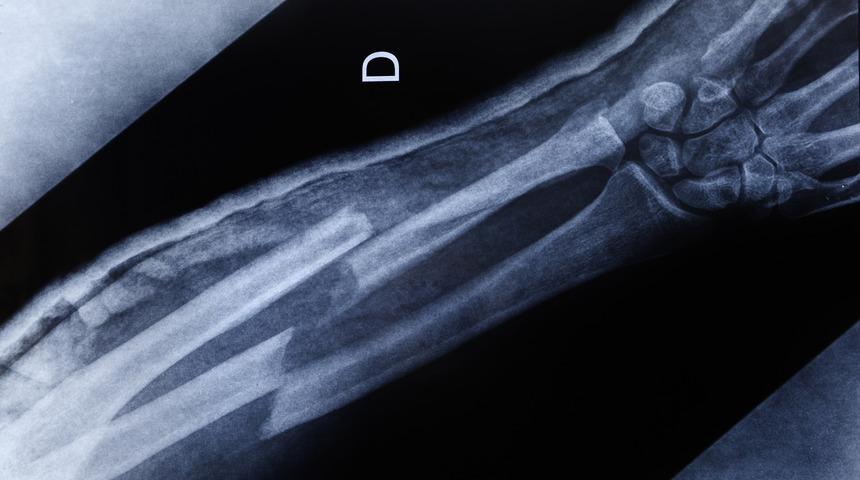

Kırık kemiklerin kaynamamasında sigaranın etkisi olduğunu söyleyen uzmanlar, kemik kaynamasında sigara kullananlara uyarılarda bulunarak, sigara kullanımının kırık kemiklerin iyileşmesini geciktirdiğini söyledi.

Farklı nedenlerden dolayı kırılan kemiklerde kaynamanın gecikmesi veya kaynamanın olmaması, yaş, cinsiyet, beslenme ve yaşam biçimi gibi birçok etkene bağlı olarak gerçekleşiyor. Sigara kullanımının kemik kaynamasını geciktirdiğini vurgulayan uzmanlar, beslenme ve şeker hastalığı gibi faktörlerin de kaynamanın gecikmesinde etkili olduğuna dikkat çekiyor. Uzmanlar, kemik sağlığı için D vitamini açısından zengin olan güneş ışınları ile kalsiyum ve protein açısından zengin yiyeceklerden faydalanılmasını öneriyor.

KEMİK 5,5-6 AYDA KAYNAMADIYSA CERRAHİ MÜDAHALE GEREKİR

Kırıkların çok kolay oluştuğunu fakat kaynamasının karmaşık bir süreç olduğunu belirten Prof. Dr. Mehmet Kerem Canbora, “Cerrahi olarak ya da cerrahi dışı kırıkların çoğunu kaynatıyoruz. Yıllar önce kırığın kaynaması için beklenen süre bu 9 ay gibi bir süreydi. 6-9 ay gibi bir sürede filmde, radyolojide ya da klinik olarak kaynama belirtilerini alamıyorsak kaynamıyor diyebiliyorduk. Günümüzde o süre birkaç ay kısaldı. En çok kırılan kaval kemiği üzerinden örnek verebiliriz. Kapalı bir kırığı, cerrahi bir ameliyatla ya da küçük bir çocukta alçıyla tedavi etsek de fark etmiyor. Bu süreçte dolaşım takibi ve röntgen takibi ile öngörülen bir yüklenme süresi vardır. Kırığa bakarak tahmin ederiz, çok standart değildir ama aşağı yukarı 6-8 haftalık bir süreden bahsedebiliriz. Önce yavaş yavaş üzerine bastırır, sonrasında tam yüklenme uygulatırız. Yetişkin bir kaval kemiğinin kaynaması için beklenen süre 2 – 2.5 aydır, eğer 3 - 4 aylara uzadıysa ve röntgende kaynamaya dair bir belirti yoksa daha yakın takip gerekir. Çekilen 4 röntgenin en az 3’ünde kaynamaya ait bulgu bulunamadıysa, süre aşıldıysa kaynama gecikti diye düşünebiliriz. 5.5 - 6 ay geçtiyse ve hala kaynamadıysa bunun kaynamayacağına kanaat getirip, enfeksiyonu göz önünde bulundurarak yalancı eklem oluşmasını da engellemek için cerrahi müdahaleyi planlamak gerekiyor” dedi.